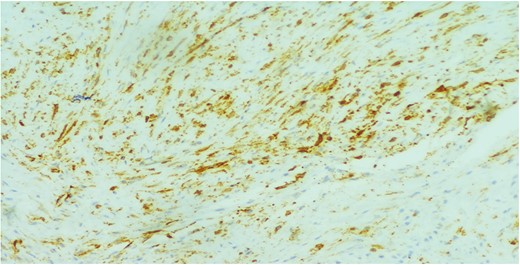

A 26-year-old female presented to our unit with recurrent right breast lump that was excised 6 years before with no available documented data. Physical examination revealed hard painless swelling occupying the medial quadrant of the right breast below the site of the old incision with no clinically palpable axillary LNs. Ultrasonography reported an ill-defined heterogeneous hypoechoic soft tissue lesion. Core needle biopsy revealed dense collagen bundles. Excision of the mass was done and paraffin sections stained by Hematoxylin and Eosin (H&E) showed benign tumoral proliferation formed of spindle cells arranged in small clustered fasicles separated by thick collagen bands (Fig. 1). Further IHE studies confirmed the diagnosis of fibromatosis supported by positive nuclear staining for B-catenin (Fig. 2). And 18 months later, she came with abdominal wall swelling, underwent CT scanning and found to be multiple soft tissue masses at the lower anterior abdominal muscles at the right lumbar and iliac regions.The largest measured ~13 × 10 cm. Core needle biopsy revealed spindle cell proliferation consistent with fibromatosis confirmed by positive reaction for SMA (Fig. 3) and B-catenin. Lesions were excised with free margins and reconstruction of the abdominal wall was carried out using a double face mesh. Final pathology report was consistent with fibromatosis confirmed by positive reaction for SMA and B-catenin.The patient had smooth postoperative course.

The cells showed diffuse positive nuclear staining for B-catenin (×200).